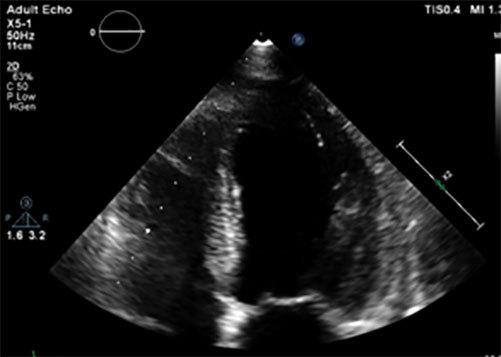

A 56-year-old woman presented with cognitive impairment, confusion and slowed speech, muscle cramps and peripheral paraesthesia preceded by vomiting. Blood tests revealed severe hypokalaemia, hyponatremia, hypomagnesemia and hypocalcaemia. Following a diagnosis of Takotsubo cardiomyopathy based on ultrasonography, the patient was treated with electrolyte supplementation and recovered within 48h. When heart failure is suspected, electrolyte abnormalities should be carefully ruled out as they can affect cardiac function.

一名56岁女性出现认知障碍、意识模糊、言语迟缓、肌肉痉挛和周围感觉异常,之前有呕吐症状。血液检查显示严重低钾血症、低钠血症、低镁血症和低钙血症。基于超声心动图诊断为应激性心肌病后,患者接受了电解质补充治疗,并在48小时内康复。当怀疑心力衰竭时,应仔细排除电解质异常,因为它们会影响心脏功能。